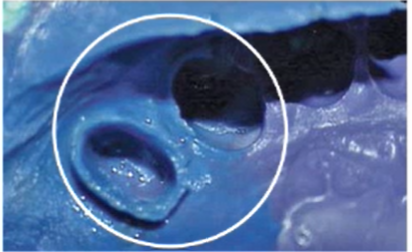

ID problem + cause + solution

A

Inhibited / slow setting

cause: For PVS materials: Sulfur inhibition due to contact of latex gloves with impression material

Or

Residues from temp crown or cement present

Soln:

1. Wear gloves without sulfur

2. Fabricate temp crown after final impression has been made

3. Remove air-inhibited layer on exposed surface with alcohol wipe before final imp